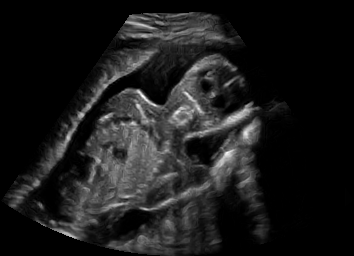

US simulation. We used a ray-tracing framework to render B-mode images from a geometric fetal model, by simulating a convex probe placed at multiple locations and orientations on the abdominal surface, with imaging settings listed in Tab 1. At each location, simply rasterizing a cross-section through the triangulated anatomical surfaces at the ultrasound center imaging plane provided corresponding semantic maps. Fig. 3 shows example B-mode images with corresponding semantic maps. A total of simulated frames were resized to and randomly split into training-validation-test sets by 80-10-10%.

In Fig. 3 we show that only learning an auxiliary seg-to-real translation, i.e. CUT+S, cannot guide the network to learn the semantics of simulated images.

CUT+SC with the loss term largely reduces hallucinated image content, although it still fails to generate fine anatomical details. With the multi-domain conditional generator and additional losses of ConPres, translated images preserve content and feature a realistic appearance. Training without leads to training instability.

Comparison to state-of-the-art. As seen qualitatively from the examples in Fig. 3, our method substantially outperforms the alternatives in terms of content preservation, while translating realistic US appearance. CycleGAN, SASAN, and CUT hallucinate inexistent tissue regions fail to generate fine anatomical structures, e.g. the ribs. StarGAN fails to generate faithful ultrasound speckle appearance, which leads to highly unrealistic images. Our method ConPres preserves anatomical structures, while enhancing the images with a realistic appearance. It further faithfully preserves acoustic shadows, even without explicit enforcement. However, as seen from the last column, the refraction artefact appears artificial in the images translated by all the methods. Note that although the imaging field-of-view (FoV) and probe opening in the simulation is significantly different from the real in-vivo images (Fig. 2) used for training, our ConPres maintains the input FoV closely compared to previous state-of-the-art. The results in Tab 2 quantitatively confirm the superiority of our method. Note that SSIM and FID/KID are used to measure translation performance from two different and sometimes competing aspects, with the former metric for quantifying structure preservation and the latter metrics for image realism.